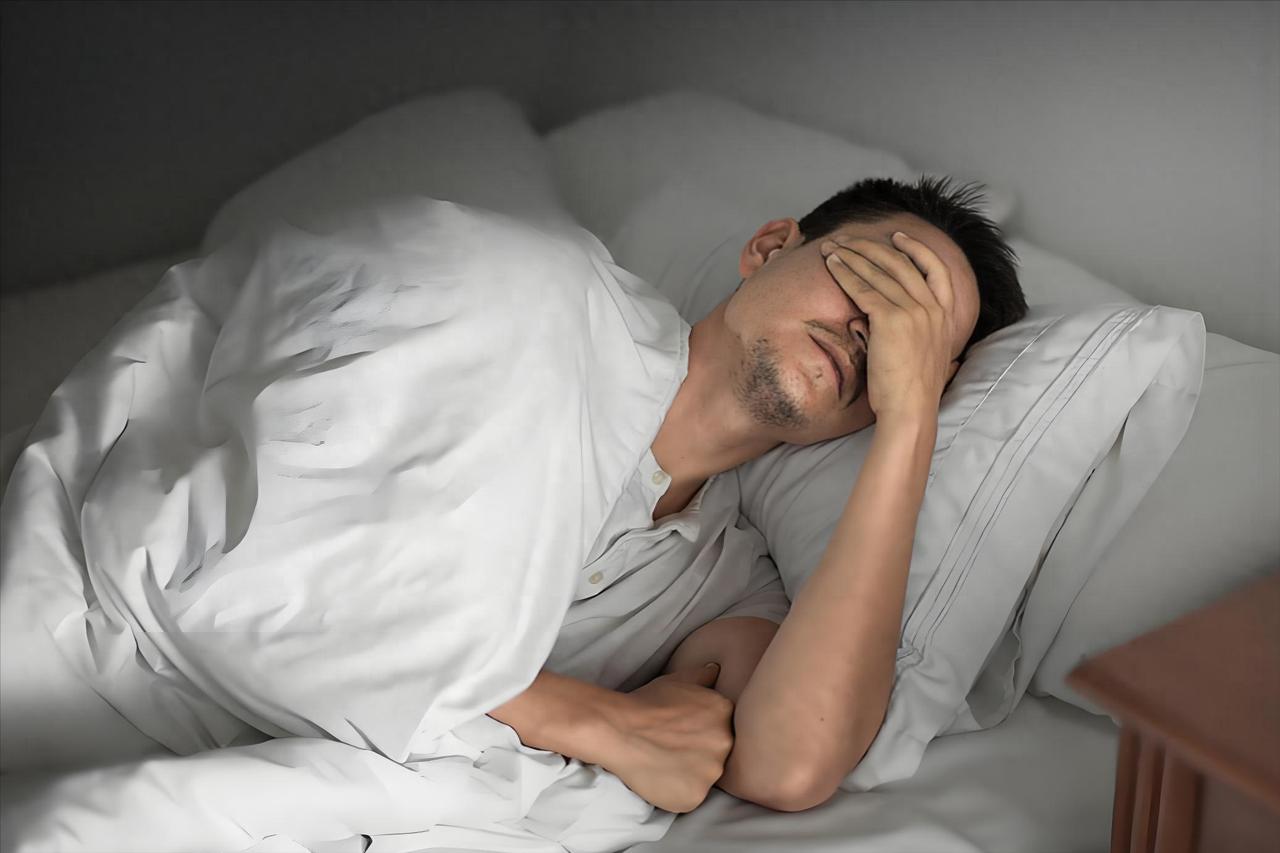

肾气一虚,尿频难止!千古良方温肾阳、固膀胱,告别一夜起夜十几次 我是中医陈大夫,内容仅作健康科普,不做医疗建议,不适请及时就医。 一晚上跑厕所七八次、十几次,刚躺下又想尿, 尿不尽、滴滴答答、腰膝酸软、手脚冰凉, 这不是喝水多,是肾气不足、膀胱不约。 肾主水、司二便,肾阳一虚,膀胱关不住, 光吃利尿、消炎的没用,必须温补肾阳、固摄膀胱。 千古良方 ——缩泉丸,就是专门治这个的。 缩泉丸:三味药,温肾固尿,一觉睡到天亮 只有简单三味: 乌药、益智仁、山药 益智仁 温肾暖脾,固精缩尿,把肾气收住, 让膀胱 “关得紧”,不再频繁漏尿、起夜。 乌药 温通膀胱、散寒止痛, 把下焦寒气散掉,尿道不再受刺激。 山药 健脾固肾、平和补养, 稳固根本,不让肾气再虚。 三药合用: 温而不燥,补而不腻 一边把肾阳补起来,一边把膀胱固住, 尿频、尿急、夜尿多、尿失禁,一次调到位。 适合这些人 夜尿频繁,一晚 3 次以上 小便清长、滴滴答答、尿不尽 腰膝冷痛、畏寒怕冷、手脚冰凉 中老年尿频、前列腺问题引起的夜尿多 咳嗽、走路就漏尿的人群 一句话总结: 尿频根源在肾虚,光治膀胱没有用; 温肾固尿缩泉丸,夜尿减少睡得安!